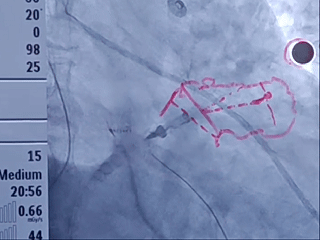

封堵器完全释放

右前斜

右肩位

左前斜位

肝位

多角度观察心包积液情况,无新增心包积液,同时封堵器稳定封堵心耳口部。